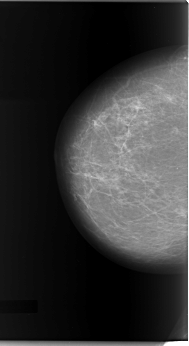

C_0081_1.RIGHT_CC

RIGHT_CC LINES 5872 PIXELS_PER_LINE 3208 BITS_PER_PIXEL 12 RESOLUTION 50 NON_OVERLAY